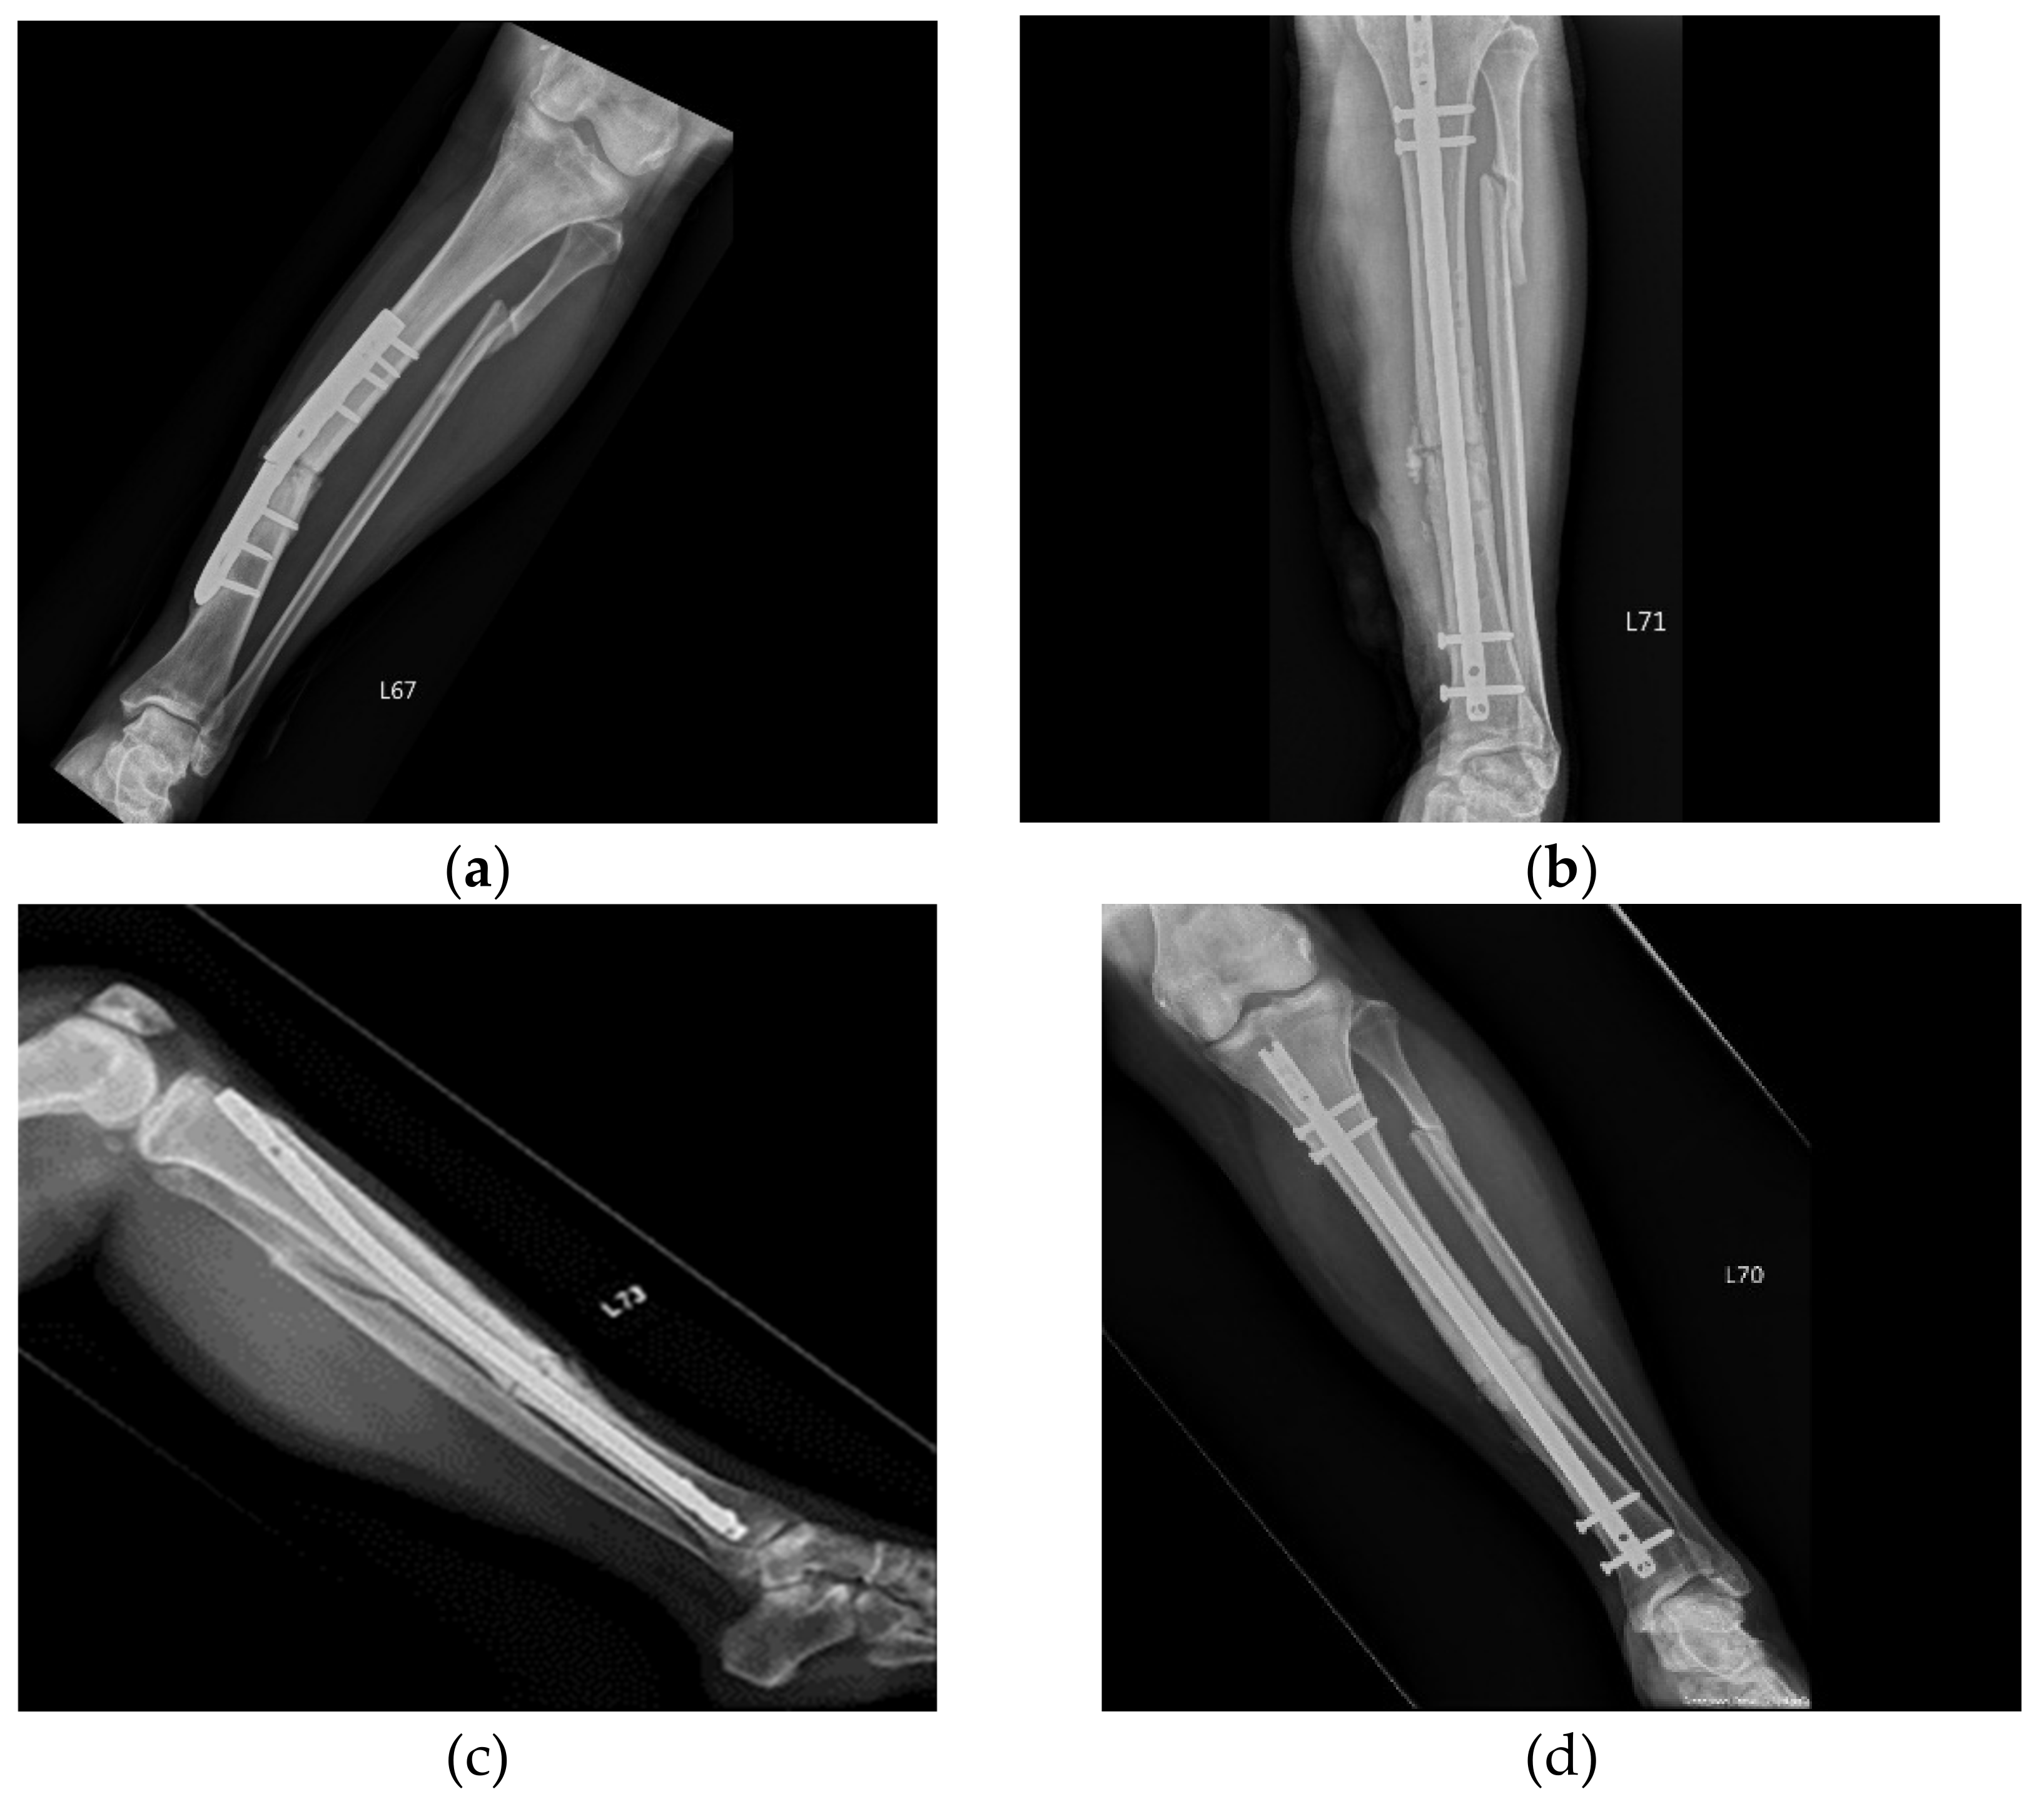

| 1 | 50 | Female | Tibial fracture | Plate implant failure, followed by intramedullary nail at 9 months but still non-union | 9 | 3 | Union |

| 3 | 45 | Male | Right tibia and fibula fracture | Dynamization of distal screws on tibia; ACS injection was given on fibula. | 9 | 3 | Union |

| 10 | 21 | Female | Right upper tibia fracture | Non-union after ORIF | 12 | 3 | Union |